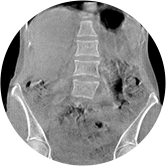

髖關節

腰椎